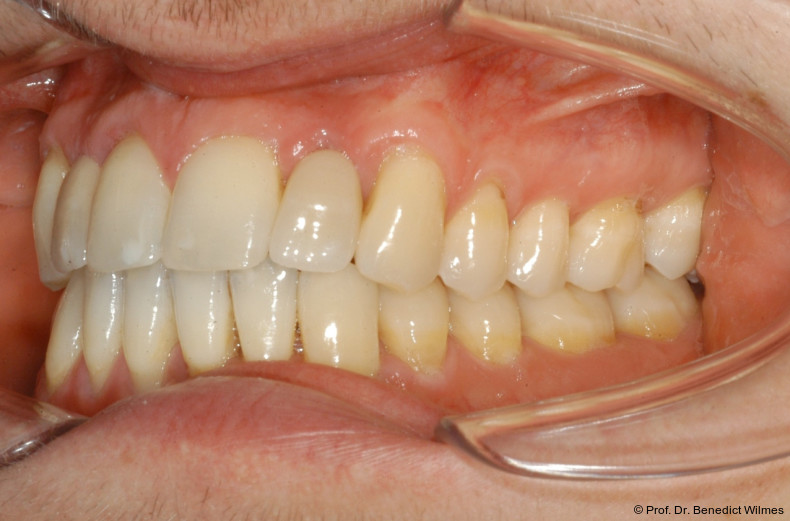

Ein 14-jähriger Patient wurde bei Aplasie der beiden oberen seitlichen Schneidezähne mit dem Ziel der beidseitigen Lückenöffnung kieferorthopädisch therapiert (Abb. 1a+b). Zum Ende der kieferorthopädischen Behandlung wurden zwei Miniimplantate in Regio 2er als temporärer Zahnersatz inseriert (Benefit System, PSM, 2 x 13 mm, Abb. 2a+b). Nach Abdrucknahme wurden Kronen auf den Peek-Abutments modelliert und diese mit Kunststoff auf die Abutments geklebt (Abb. 3a–d). In den Abbildungen 3 und 4 sind die klinischen und röntgenologischen Nachkontrollen innerhalb der nächsten achteinhalb Jahre dokumentiert. Man erkennt einen sowohl in der Höhe als auch in bukkopalatinalen Breite verbleibenden gesunden Knochen ohne Anzeichen einer Atrophie. Im Alter von 23 Jahren wurden die definitiven Implantate ohne die Notwendigkeit einer Augmentation eingesetzt (Abb. 5) und nach Einheilung prothetisch versorgt (Abb. 6a–e und Abb. 7a–c).

Bei einer elfjährigen Patientin fehlten bei Zustand nach Frontzahntrauma im Alter von neun Jahren beide oberen mittleren Schneidezähne (Abb. 8a+b). Als temporärer Ersatz wurden Miniimplantate (Abb. 9, 2 x 13 mm) eingesetzt und Kronen im Labor angefertigt, welche auf den Miniimplantaten verschraubt wurden (Abb. 10a+b). Die Miniimplantate wurden im Alter von 19 Jahren, also nach achtjähriger Nutzung (Abb. 11a+b), durch dentale Implantate ersetzt.